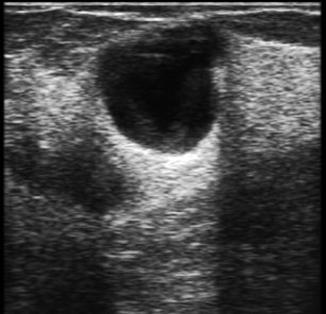

Absceso mamario:

Es una acumulación encapsulada de pus dentro del tejido mamario.

♦ Masa fluctuante a la palpación

♦ Aspiración con aguja: para abscesos con piel suprayacente intacta

♦ Incisión y drenaje: si la piel que recubre tiene necrosis